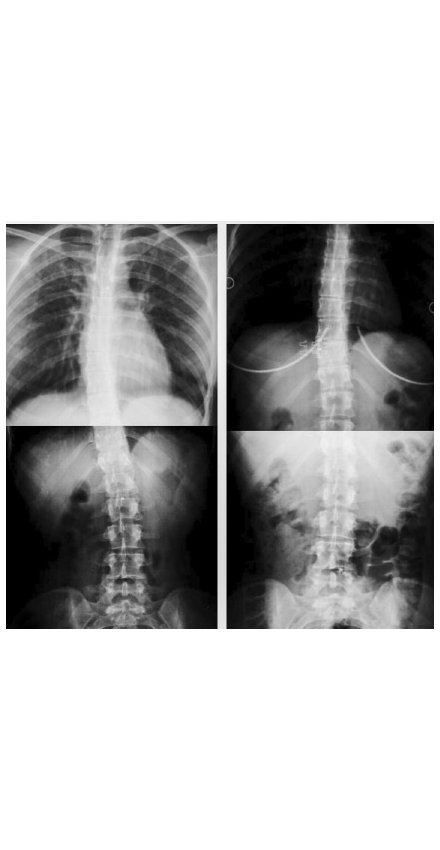

SKOLYOZUM 9 DERECE AZALDI

''İlk görüşmemizde Elif Hanım bana 30 seanslık özel bir program önerdi. Dü zenli çalışırsam ve egzersizleri doğru yaparsam ağrılarımın ciddi derecede azalacağını söylediğinde çok sevindim. Nitekim öyle de oldu. Seanslarım hala devam ediyor olmasına rağmen kendi mi çok iyi hissediyorum. Elif Akıncı Pozitif Yaşam Merkezi sayesinde egzer sizler hayatımın bir parçası. Başta Elif Hocam olmak üzere, buradaki hocala rımızın ilgi ve alakası muhteşem. Yak laşık 2 ay süren kapanma sürecinde de evde kendi imkanlarımla egzersizleri me devam ettim, unuttuğum egzersiz ler için hocalarımla hep görüşme ha lindeydim. Aileden farksız, güler yüzlü bir şekilde bana yardımcı oldular, hiç bir sorumu cevapsız bırakmadılar. ELİF HOCA BENİM ŞANSIM Seanslarım sonucunda kontrol için röntgen çektirdim ve gözlerime ina namadım. Hemen sonuçları yakın çevremle paylaştım. Herkes nere ye gittiğimi ve nasıl böyle bir ilerle me kaydettiğimizi sordu. Başkalarına dahi benim referansımla burayı öne receklerini söylediler. Sonuçları gör dükten sonra tamamen emin oldum ki Elif Hocam ile yollarımız kesiştiği için çok şanslıyım. Herkese tavsiye ederim. Buradan da kendisine tekrar teşekkür ederim.”